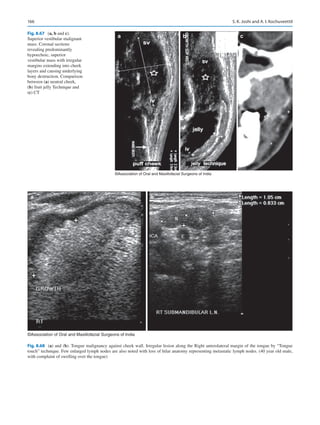

their cancers even before they see their doctor, today. Where

does that place a specialist in the future?

In a keynote address at the Royal College of Surgeons in

London at the 50th anniversary of the IAOMS, Brian Schmidt